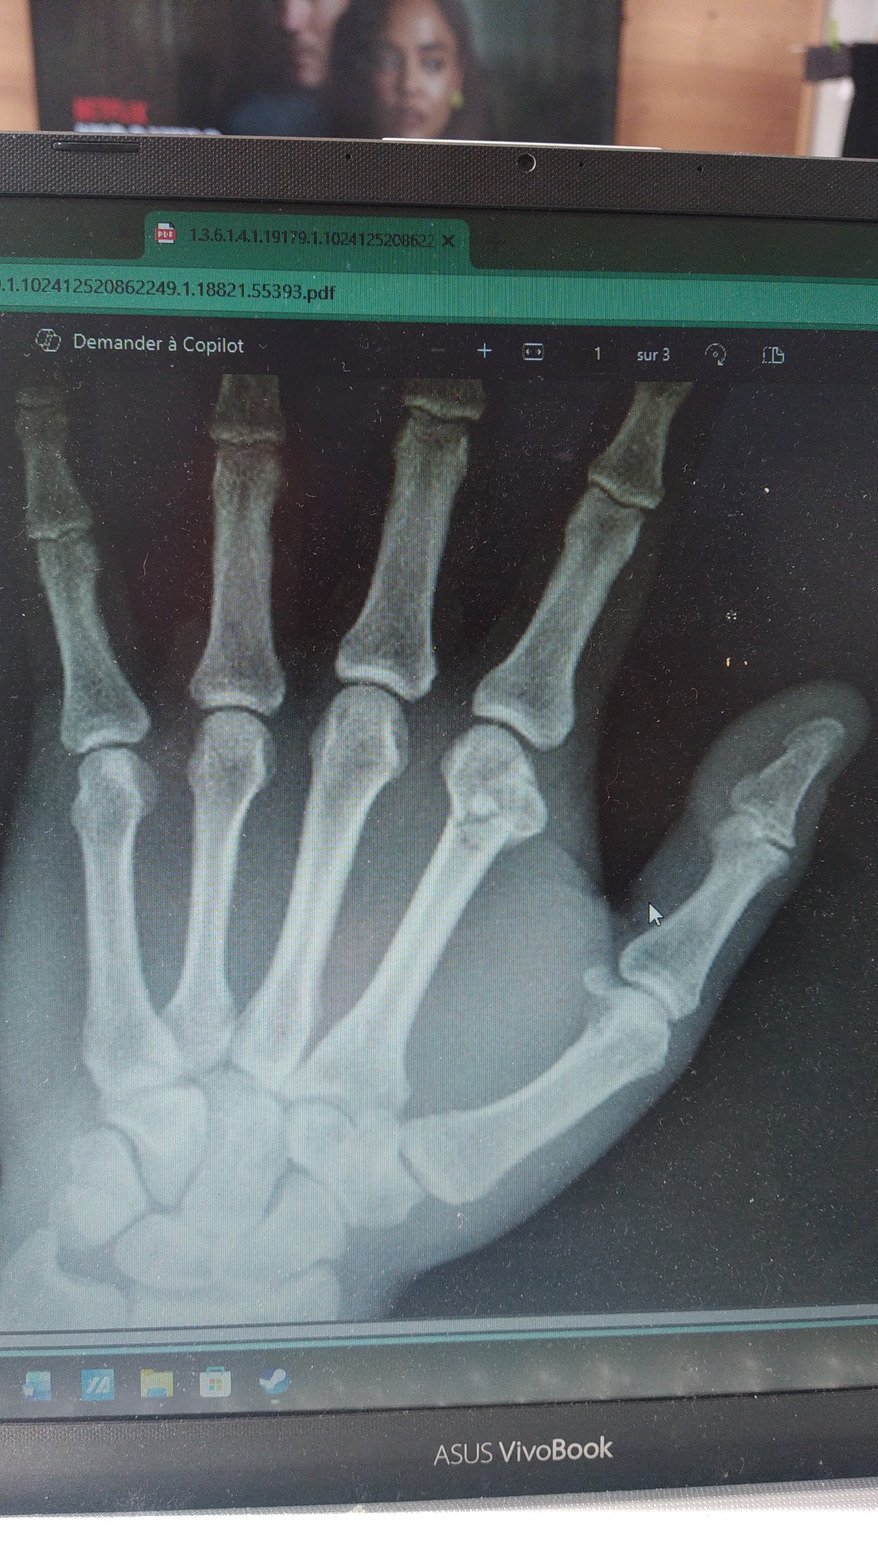

Je vous fais grâce des détails mais cab medical radio fracture métacarpe pas très jolie ça tourne un peu...je vois au moins 2 traits de fracture

Plâtre avis chir de la main dans la semaine...